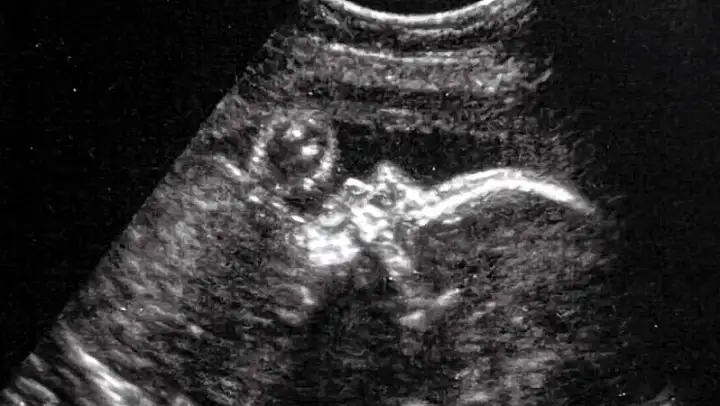

Ultrason kullanarak atardamarın tespiti yöntemiyle gerçekleştirilen ameliyat, bebeğin henüz anne karnındayken gerçekleştirildi. Doktorlar, annenin karnından uzun bir iğneyi bebeğin beyninin etkilendiği kısma yönlendirdi ve daha sonra damarlara geri akışı engellemek amacıyla bir madde enjekte etti.